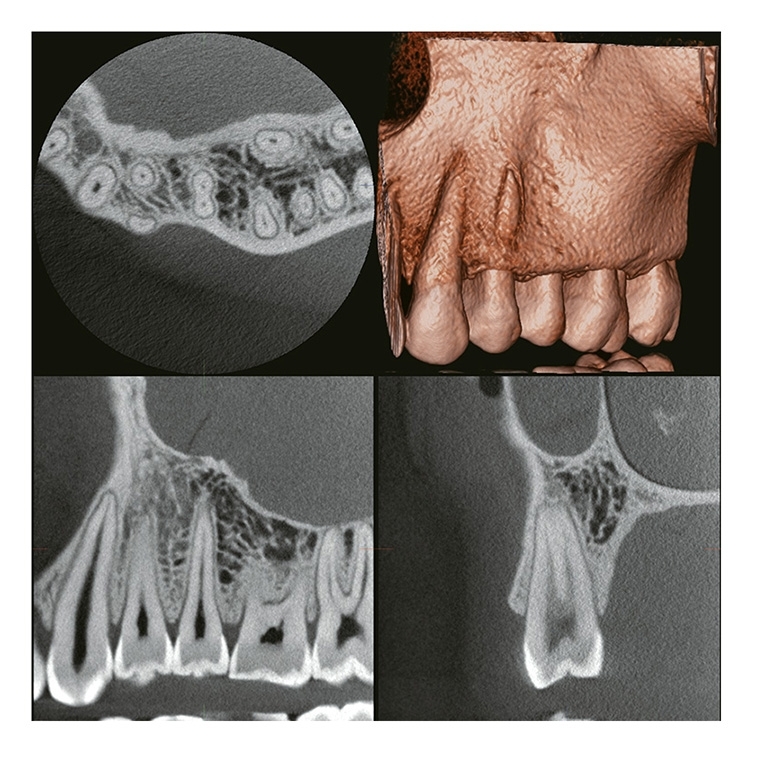

2 VERAVIEW (X800) CP (S) / (M) / (L)

Information / DemoPanorama/Cephalostat 3D & 2D

FOV bis zu: Ø 150 X H 140